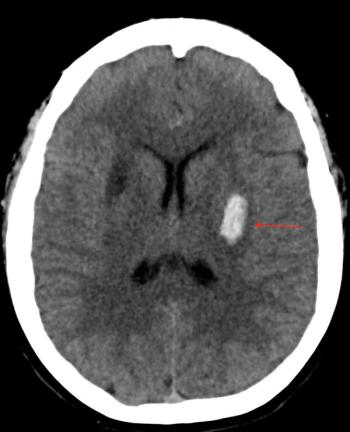

A 39-year-old male with a past medical history of hypertension and depression woke up with a severe headache, difficulty speaking, and right-sided weakness. Read the case details here.